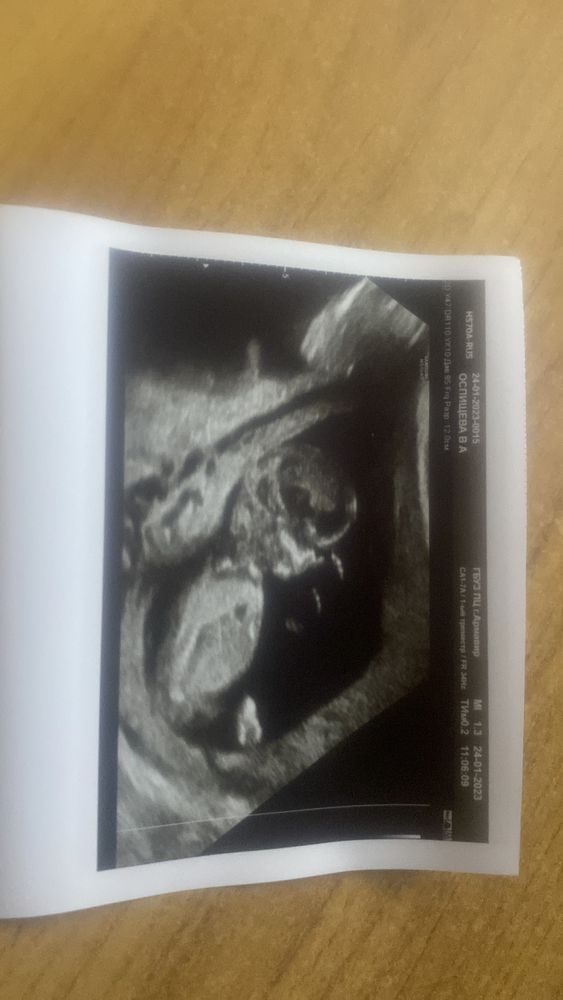

Результаты: УЗИ, КТГ, доплера, скринингаПривет всем ! Уже писала в другом сообществе😉 сегодня прошла первый скрининг. Все хорошо. ЧСС 158. Пол не смогла разглядеть 🤭 вертелся как мог 😂. Ниже фото будет, может кто что увидит. (Значек поставила на удачу 😄).

и еще , поставили прикрепления к плаценте центральное, по передней стенки, ранее ставили предлежание хориона , сейчас говорят поднялось. Читаю в интернете все равно риски есть